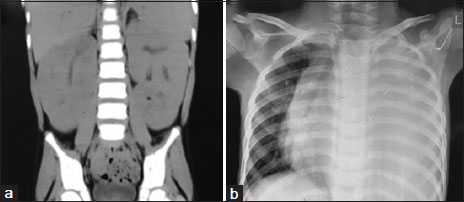

confirmed bilateral enlarged kidneys with coarse echotexture. Abdominal computed tomography scan confirmed the

large-sized kidneys [Figure 1]a. His electrolytes, liver function test, calcium (7.8 mg/dl), phosphorous (3.2

mg/dl), lactate dehydrogenase (256 U/L), and uric acid (1.2 mg/dl) done were within normal range. The chest X-ray

showed moderate left-sided pleural effusion [Figure 1]b. Arterial blood gas analysis showed pH - 7.38, pCO2 - 26 mmHg, pO2 - 54 mmHg,

| Figure. 1 (a) Abdominal computed tomography images showing the bulky kidneys performed on admission to the tertiary hospital. (b) The chest X‑ray showing left-sided pleural effusion